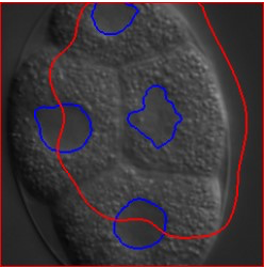

学習時には正しく領域を抽出できる場合でも、撮影条件が変化すると同じモデルでは対応できないことがあります。

例えば、対象や顕微鏡が同じでもカメラなどが異なるだけで、予測精度は大きく低下します(青:正解データ,赤:推定結果)。